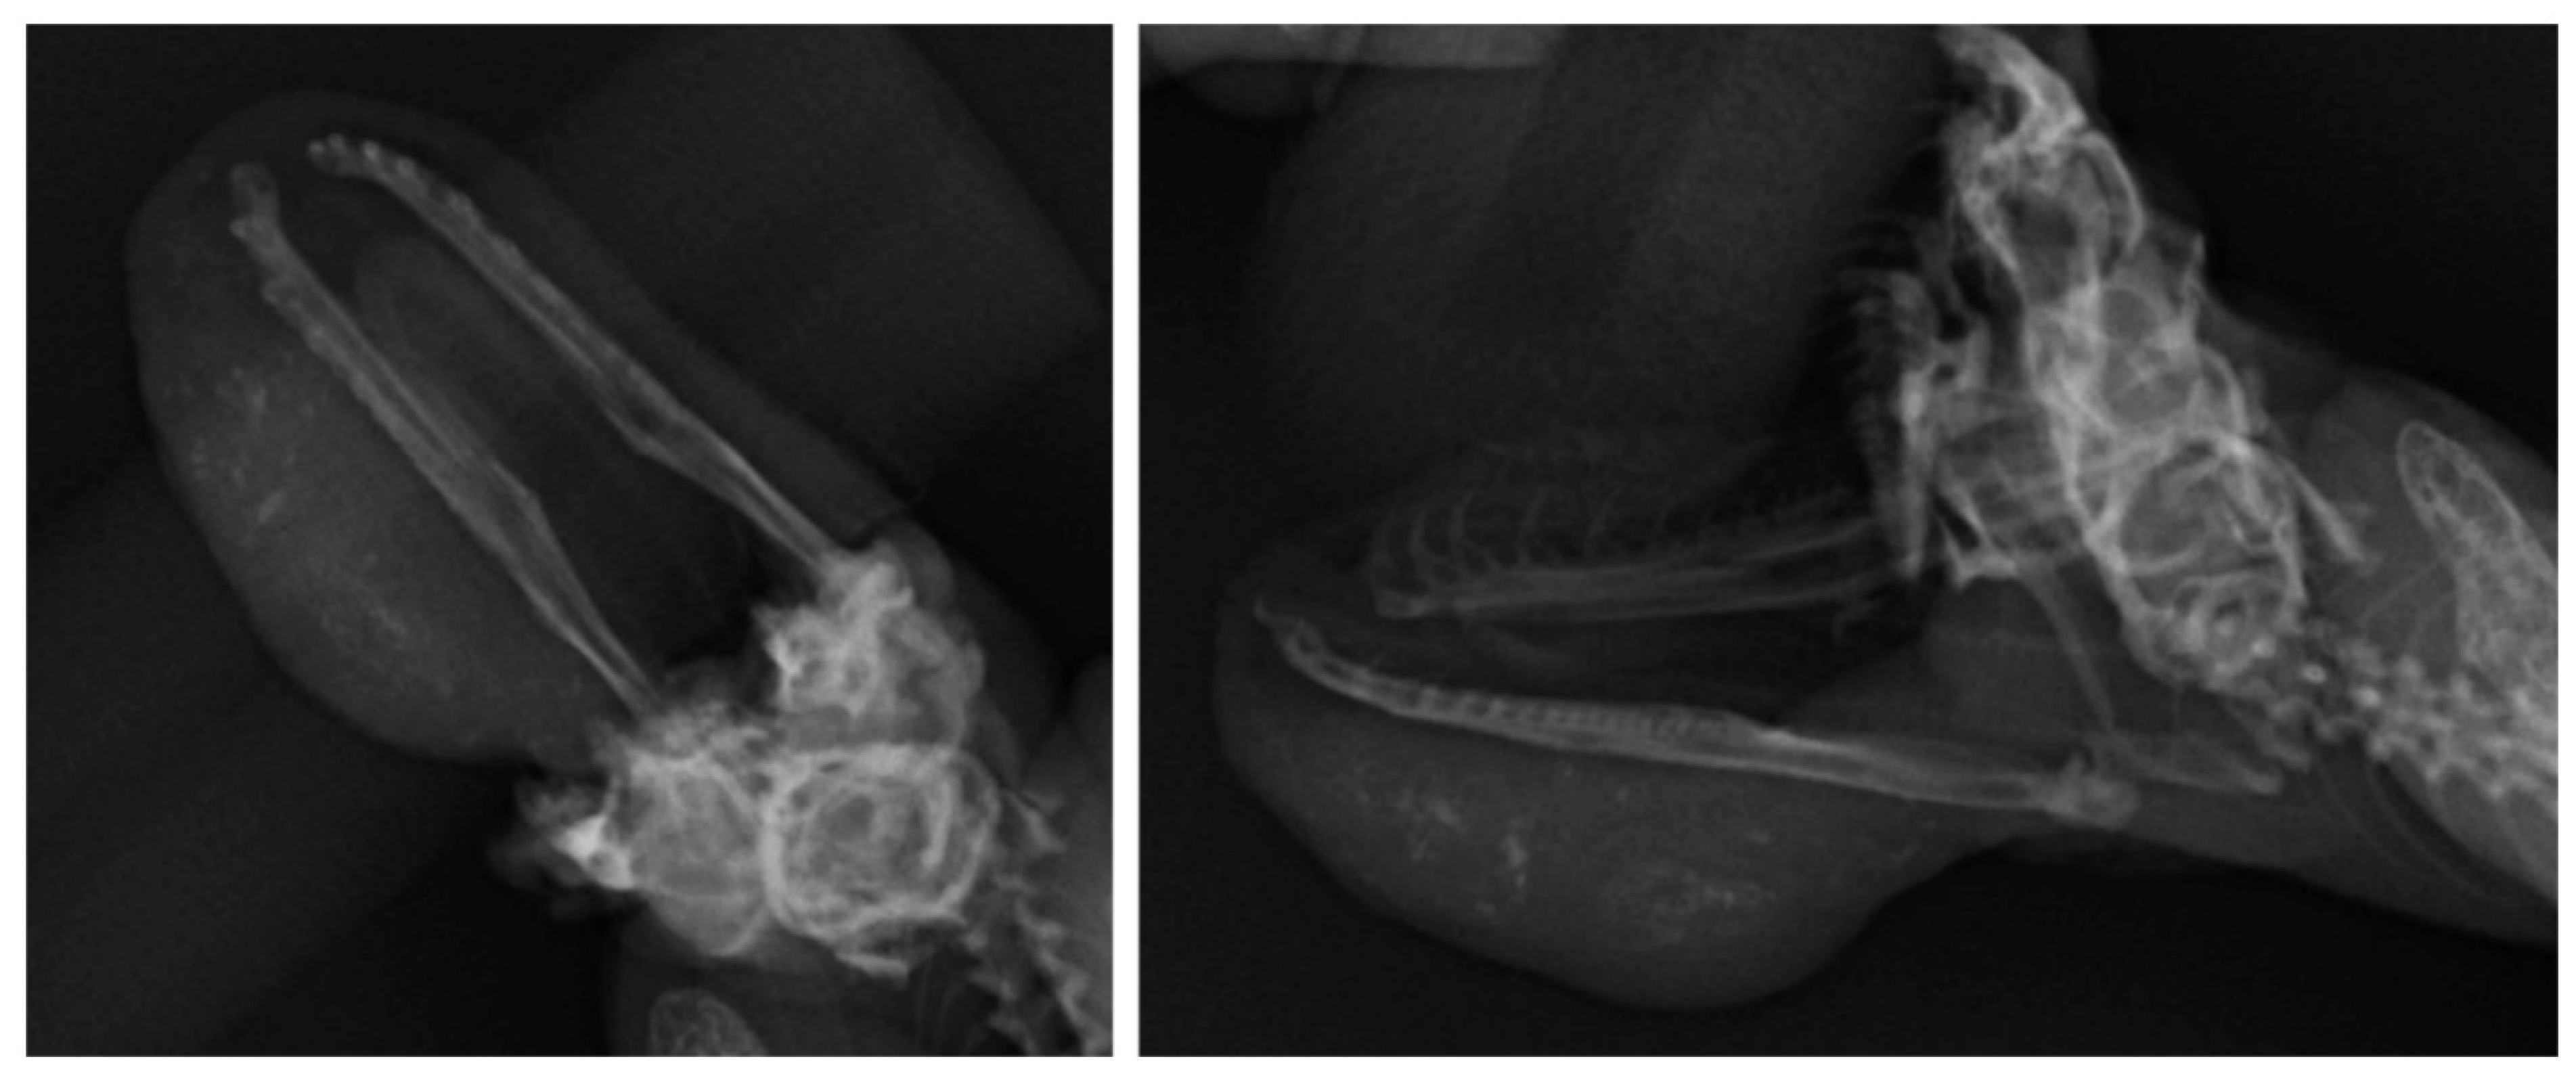

Radiographs were performed to evaluate the submandibular mass and lungs. The submandibular mass showed multi-focal radiopaque lesions, which were suspected to be calcifications, and there was no evidence of mandibular bone invasion or lung metastasis (Figure 2). The patient was anesthetized via chamber induction with isoflurane. Fine needle aspiration (FNA) was performed for the cytological study. However, only tissue debris and purulent materials, such as degenerated heterophiles and bacteria, were seen on cytology. Bacterial cultures were performed on Columbia agar containing 5% sheep blood under both aerobic and anaerobic conditions at 27 °C for 24 h. One colony of the bacteria was obtained by colony morphology. The bacteria were identified as Klebsiella oxytoca by 16s rRNA gene sequencing (Macrogen, Seoul, South Korea).

Figure 2.

Radiographic examination of the submandibular mass revealed the presence of multi-focal mineralization in the area of the lesion. No evidence of mandibular invasion and lung metastasis was observed.